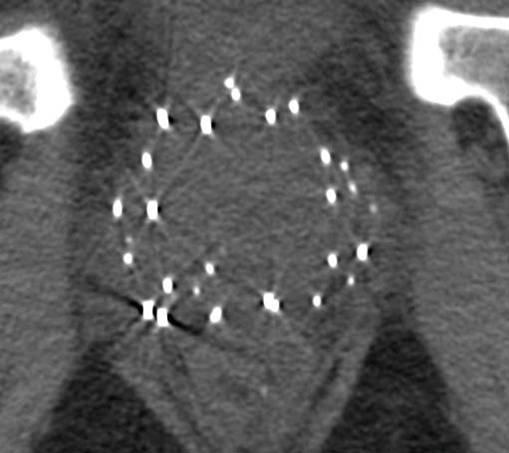

Seed auf dem Röntgenbild

Bei der Kontrolluntersuchung - werden Position und Wirkungsgrad der Stifte (Seeds) kontrolliert.

Etwa 4 Wochen nach der Implantation der Seeds wird eine Qualitätskontrolle der Operation durchgeführt, um sicher zu stellen, dass auch wirklich das gesamte Prostatagewebe mit einer ausreichend hohen Strahlung versorgt wurde. Ein Kernspin-und /oder Computertomogramm erfasst exakt die Lage der implantierten Seeds. Ein Computerprogramm berechnet dann nochmals die applizierte Strahlendosis.